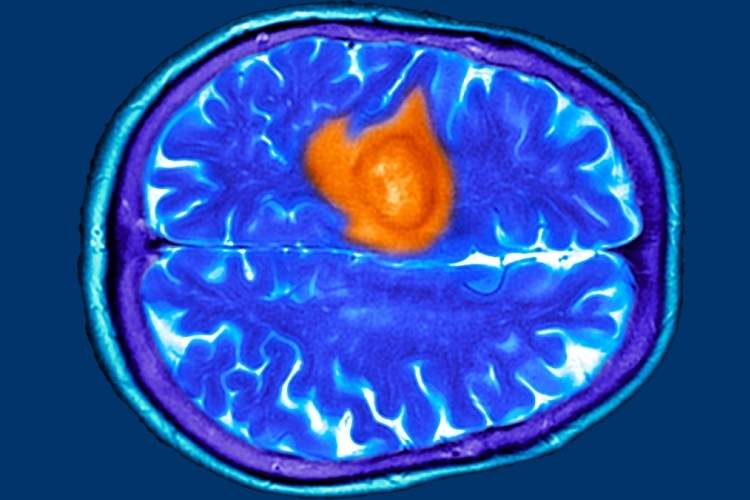

به گزارش بیکینگ و به نقل از ساینسآلرت، پژوهشهای اخیر نشان میدهد که بیماران و پزشکان عمومی در مراحل اولیه اغلب این نشانهها را نادیده میگیرند و همین امر باعث تأخیر در تشخیص میشود. از آنجا که درمان تومور مغزی در مراحل پیشرفته دشوارتر است، شناسایی علائم اولیه اهمیت ویژهای دارد.

تومور مغزی میتواند با علائمی مشابه بیماریهای رایج مانند اضطراب، عفونت سینوس یا یائسگی بروز کند. در پژوهشی که بر پایه مصاحبه با بیماران انجام شد، هفت علامت اصلی شایع اما فریبنده شناسایی شد. نخستین مورد، دشواری در یافتن کلمات است؛ برخی بیماران در صحبت کردن یا کامل کردن جمله دچار وقفه میشدند، موضوعی که ابتدا به استرس یا خستگی نسبت داده شد. دوم، مهذهنی یا Brain Fog است که با ناتوانی در تمرکز و فراموشی همراه میشود. اگر این حالت با مشکلات گفتاری یا بینایی همراه شود، نیاز به بررسی پزشکی دارد.